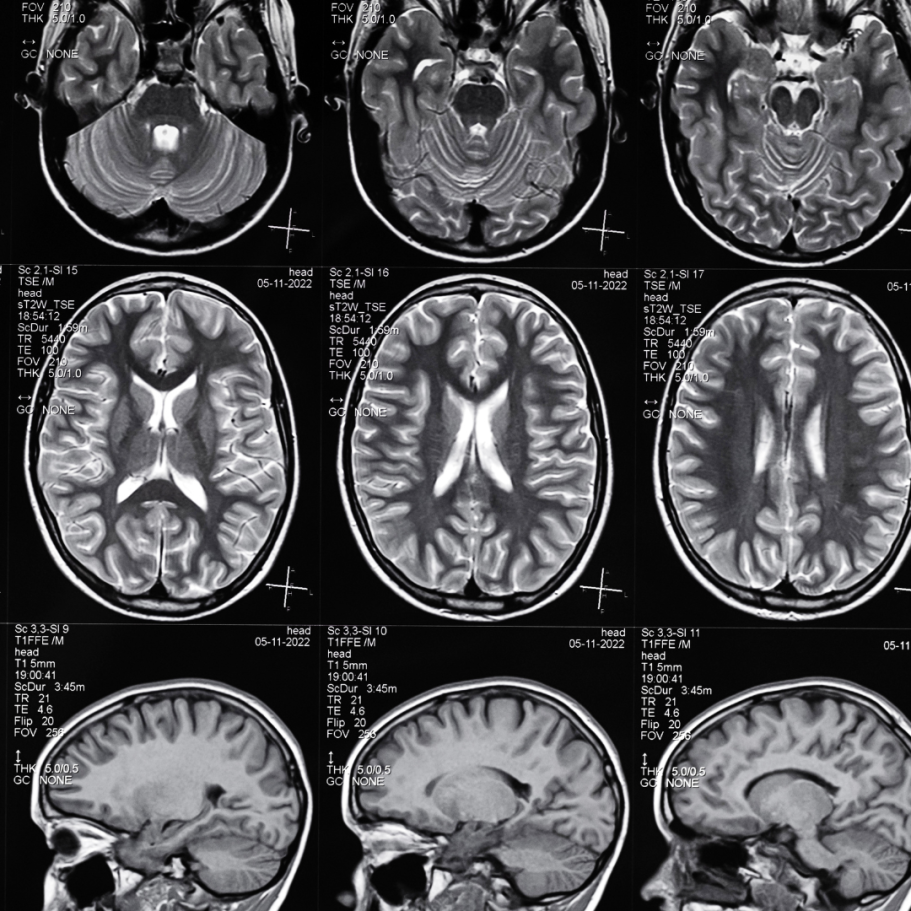

Unser Ziel ist es, funktionelle und strukturelle Bildgebungsverfahren gezielt zu nutzen, um eine möglichst präzise Diagnostik zu ermöglichen und so die Grundlage für fundierte therapeutische Entscheidungen zu schaffen. Durch die Kombination aus hochauflösender MRT, funktioneller Bildgebung (fMRT) und Traktographie erhalten wir ein detailliertes Verständnis sowohl der anatomischen Strukturen als auch der funktionellen Abläufe im Gehirn.

Dabei verbinden wir wissenschaftliche Forschung mit klinischer Erfahrung. Aktuelle Erkenntnisse aus der Forschung fließen direkt in unsere tägliche diagnostische Arbeit ein. Dieser enge Austausch zwischen Forschung und Praxis erlaubt es uns, die Neurobildgebung kontinuierlich weiterzuentwickeln und unseren Patientinnen und Patienten eine Bildgebung auf modernstem medizinischem Niveau anzubieten.